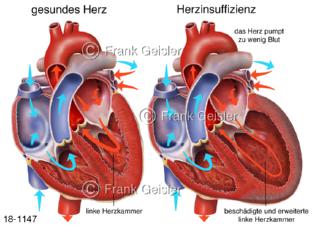

18-1147 Herzerkrankung Herzinsuffizienz, linker Ventrikel Herz mit Herzschwäche